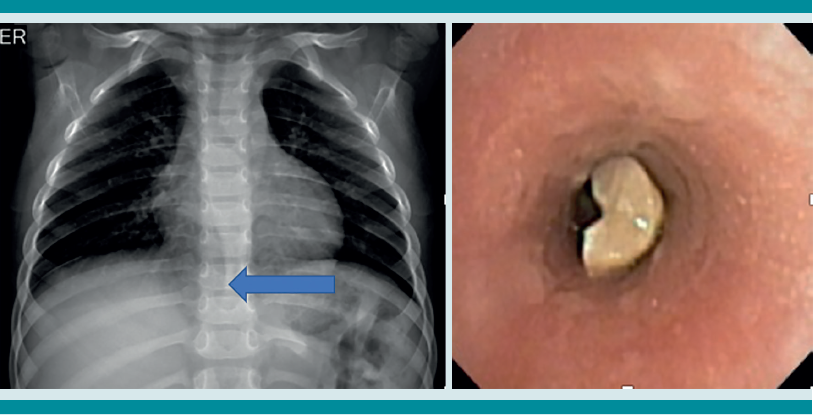

La radiografía de tórax es el primer estudio en un paciente pediátrico que llega al servicio de urgencias con sospecha de aspiración de cuerpo extraño. Gran parte de los objetos aspirados son radiolúcidos (biológicos y plásticos) y, por lo tanto, no se ven por este medio. Solo se logrará observar el cuerpo extraño en 15% de los casos (metálicos y huesos).1,6,8 Es más común identificar datos indirectos (aparecen hasta en 50% de las radiografías), que son consecuencia de la obstrucción en la vía aérea (atrapamiento de aire, atelectasias, consolidación, neumotórax) (Figuras 1,2,3,4,5). Respecto de las radiografías de tórax es que, incluso 45% pueden interpretarse normales, lo que puede resultar en un diagnóstico erróneo.1,6,9

Si al momento de consultar el paciente se encuentra en la etapa aguda, pero está estable, es decir, sin datos clínicos de inestabilidad cardiorrespiratoria, o se encuentra en la etapa oligosintomática pueden solicitarse los estudios de imagen. La radiografía de tórax es el principal recurso con el que cuentan la mayor parte de los servicios de urgencias. Es rápido, fácil, poco costoso y no requiere sedación. En caso de que sea un objeto radio-opaco, aportará el diagnóstico de manera rápida, y dará la localización del objeto (Figura 7). En caso de ser radiolúcido, la radiografía puede ser normal o mostrar los datos indirectos de obstrucción comentados. La tomografía axial computada de tórax puede considerarse si se cuenta con el recurso, tomando en cuenta lo mencionado.